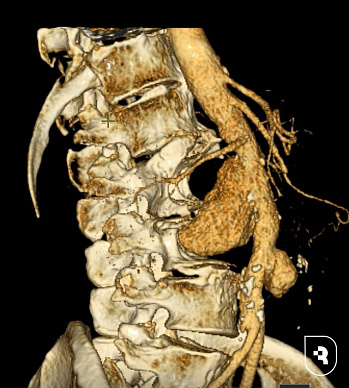

Специалисты НИИТОН СГМУ провели сложнейшую двухэтапную реконструкцию поясничного отдела позвоночника. Сначала пациенту установили полисегментарную транспедикулярную фиксацию позвоночника, обеспечив прочную стабилизацию костной ткани. Послеоперационный период прошел без осложнений. Затем, спустя месяц, была проведена обширная резекция тел пострадавших позвонков и установлен опорный металлоконструкционный имплант, позволивший восстановить целостность позвоночника и предотвратить возможные осложнения.